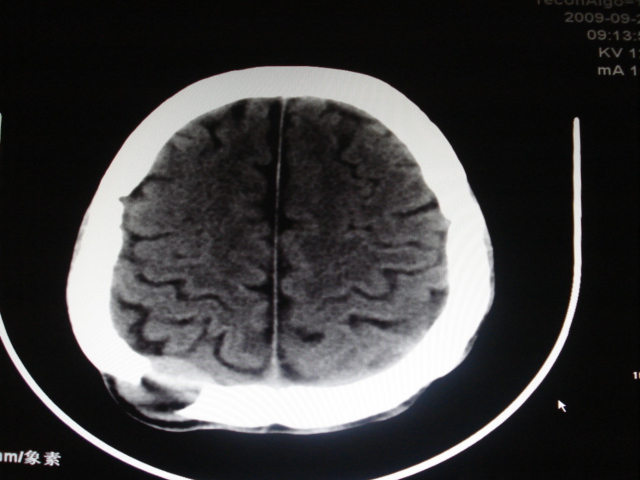

男性,48岁。发现右顶部包块一月余,质软有轻压痛。

其余没问题的层面我没有发上来,请教各位老师,可以考虑嗜酸性肉芽肿吗?